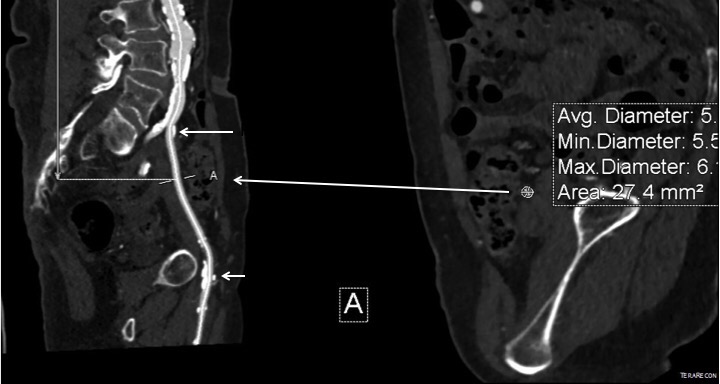

This patient presents with lifestyle limiting claudication and an absent right femoral pulse. ABI is moderately reduced on the right to 0.57, and he had no rest pain. CTA at our clinic revealed an occluded EIA bracketed by severely calcified and nearly occlusive plaque of the common iliac artery (CIA) and common femoral artery (CFA).

This has several advantages over conduit creation which can be a morbid and high risk procedure in patients who require minimally invasive approach. A graft is avoided. The artery is over 8mm in diameter where with stenting up to 8mm with an occlusive plaque, the danger of rupture is present, and often ballooning is restricted to 6mm-7mm. This is insufficient for many TEVAR grafts and TAVR valves.